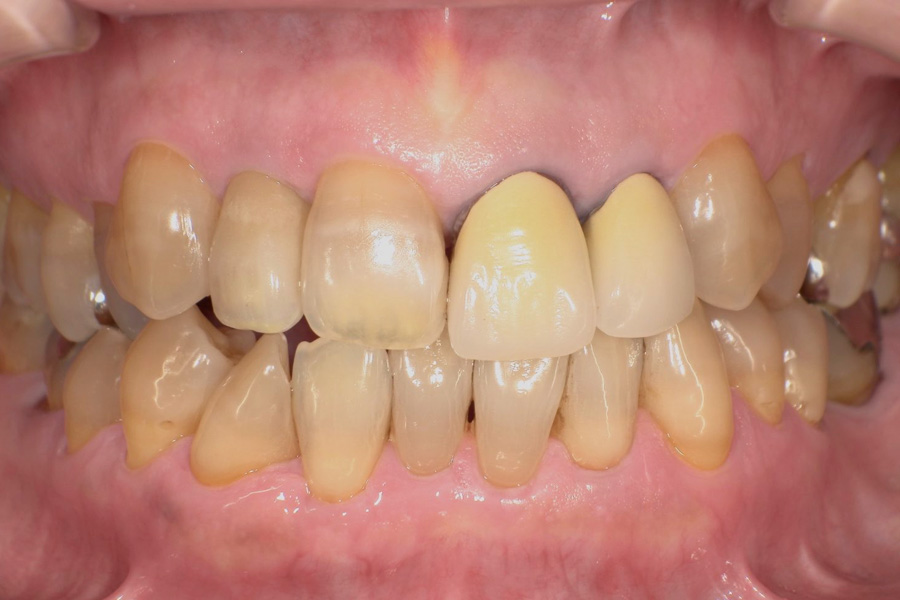

生涯、美味しく食べられる

豊かな人生を

“健口づくり”からサポートする

正しい診査診断、的確な治療をすることで、

歯だけでなく全身の健康に繋がります。

虫歯があるから削ったり悪くなったから抜くのではなく、まずは虫歯と歯周病が起きないようにより良い環境づくりをすること、そうすることによって歯を長く維持することが可能となります。